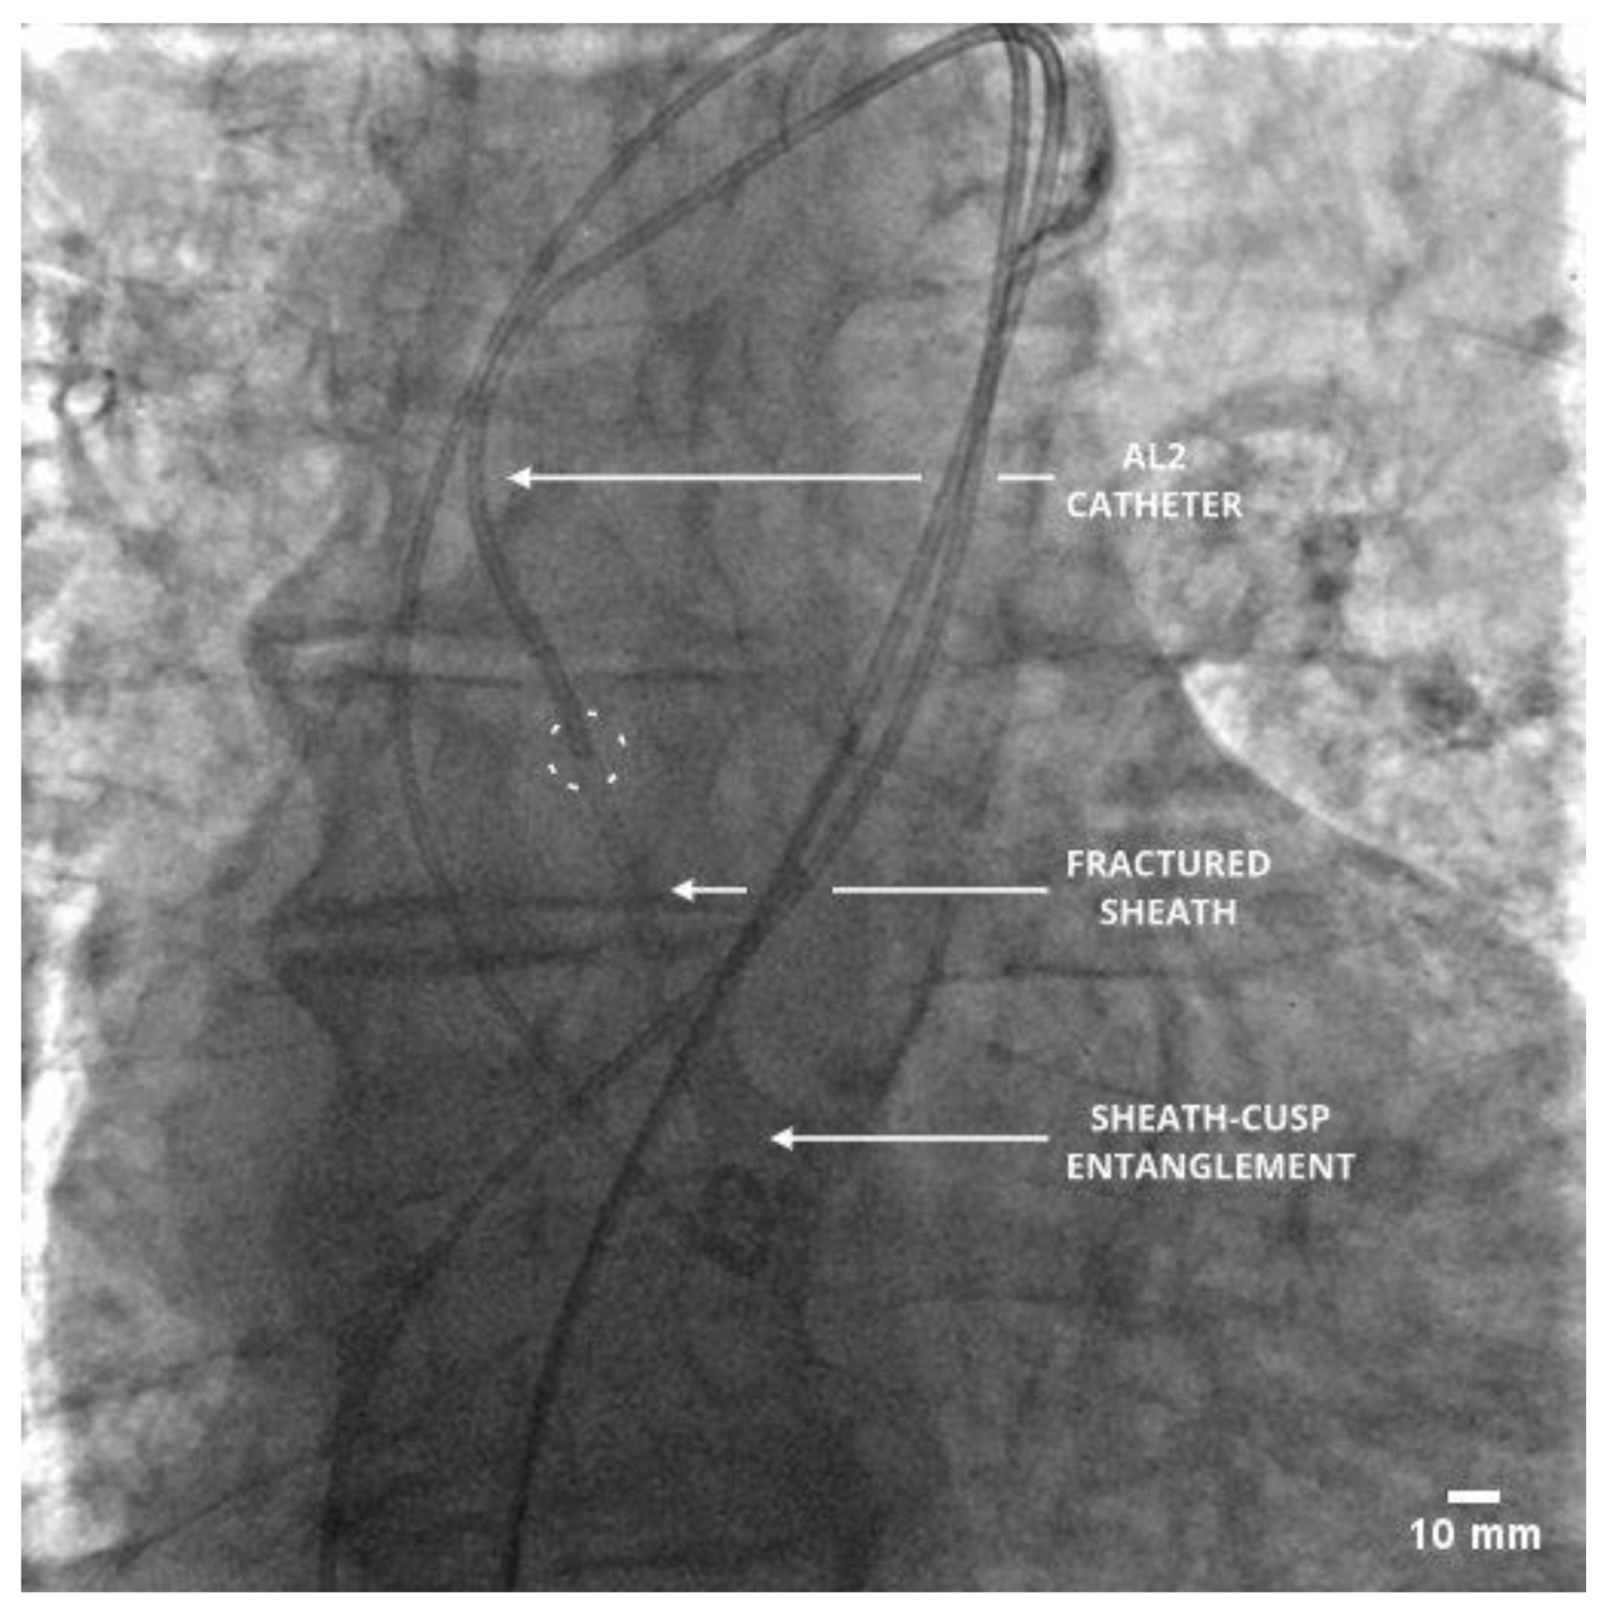

An immediate hemostatic control was established with the team strategy planning according to the Situation, Background, Assessment and Recommendation (SBAR) technique. Several unsuccessful attempts of grasping the distal sheath part with the surgical hemostat were performed. Therefore, a proximal part of the severed sheath was removed and a Medtronic Sentrant (Medtronic™, Dublin, Ireland) introducer sheath (14 French) was placed over the existing Confida wire. The Confida wire permanently remained in position with only a careful transfer from the left ventricle into the aortic bulb. This was followed by the introduction of the Amplatz Left 2 (AL2; Boston Scientific™, Marlborough, MS, USA) catheter which pushed the severed sheath in the ascending aorta over the Confida wire. The crucial step of this maneuver was the entanglement of the severed sheath in the aortic non-coronary cusp which allowed for its entrapment by the AL2 catheter (Figure 2).

Figure 2. Intra-aortic entrapment of the fractured sheath with the AL2 catheter after the Confida wire removal.